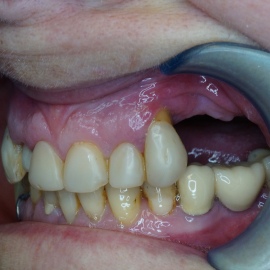

Po utracie zęba w przednim odcinku łuku zębowego należy zwrócić wzmożoną uwagę na aspekt estetyczny. Naczelnym przesłaniem odbudowy brakujących tkanek (anatomiczno-funkcjonalny kompleks tkanek: kość wyrostka zębodołowego + dziąsło + zęby) jest uzyskanie takiego wyniku, który jest najbliżej ideału, czyli takiej sytuacji jak gdyby nic się nie stało i w ogóle nie doszło do utraty zęba i tkanek około zębowych. Kluczem do sukcesu jest odtworzenie poprawnych stosunków anatomicznych: kość - dziąsło - ząb.

Korona protetyczna na implancie, funkcjonująca od roku 2003. Zdarzył się wypadek motocyklowy. Widzimy klucz do osiągnięcia sukcesu: mikrochirurgia i poprawna anatomiczna odbudowa tkanek. Tego nie zastąpi nawet najdroższy implant!

Pokazano etapową odbudowę brakujących tkanek, wraz z odbudową objętości i kształtu dziąsła.

Odbudowa tkanek i zębów przy wysokiej linii uśmiechu. Zadowalający wynik estetyczny.

Odbudowa brakującej kości, odbudowa anatomicznych stosunków dziąsła i korona całoceramiczna osadzona na łączniku cyrkonowym.